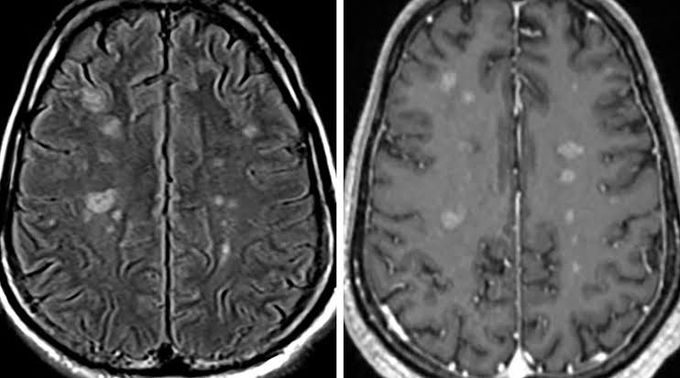

Treatment of neurosarcoidosis

There is no cure for neurosarcoidosis. Treatment of the condition occurs when patients are experiencing severe or progressive symptoms. Corticosteroids may be given to shorten and lessen the severity of the symptoms by reducing the inflammation.